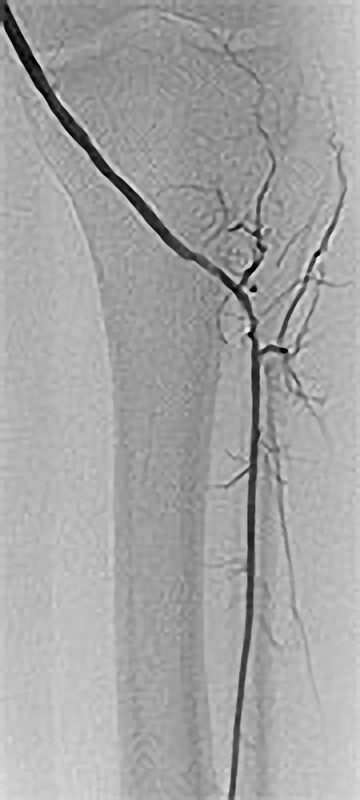

Grundprinzip der Kathetertherapie ist die Gefäßbehandlung über einen millimetergroßen Hautschnitt unter örtlicher Betäubung und das Vorschieben von Plastikschläuchen (Kathetern) in die Gefäße. Über diesen Zugang (meist in der Leisten- oder Ellenbeuge) können Gefäßeinengungen aufgeweitet oder auch Gefäßverschlüsse wiedereröffnet werden (Ballon- oder Stentverfahren). Diese Verfahren werden immer weiter entwickelt und so sind nun auch Behandlungen des Bauchaortenaneurysmatas oder das Einbringen einer Herzklappe auf diesem Wege möglich.

Möglichkeiten der Perkutanen Transluminalen Angioplastie (PTA)

Neben diesen Hauptverfahren bestehen vielfältige weitere Methoden zur Wiedereröffnung von Gefäßen, wie die Auflösung (Lysetherapie), das Absaugen (Aspiration), das Abfräsen (Atherektomie) oder Photoabladieren (Laser-Angioplastie) von Gefäßverschlüssen.

Die PTA (Perkutane Transluminale Angioplastie) im Beckenbereich ist ein minimalinvasives Verfahren zur Behandlung von verengten Beckenarterien. Dabei wird ein dünner Katheter mit einem Ballon über die Leiste in die verengte Arterie eingeführt. Der Ballon wird an der Engstelle entfaltet und dehnt die Arterie auf, um den Blutfluss zu verbessern. Oft wird zusätzlich ein Stent eingesetzt, um die Arterie dauerhaft offen zu halten. Die PTA wird meist in örtlicher Betäubung durchgeführt und ermöglicht eine schnelle Erholung. Sie ist eine bewährte Alternative zur offenen Operation bei Durchblutungsstörungen im Becken- und Beinbereich.